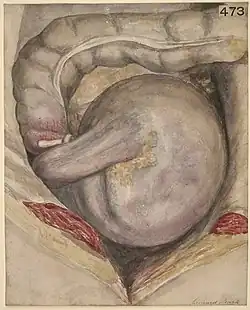

The coffee bean sign (also called the kidney bean sign, or bent inner tube sign)[1] is a radiologic sign observed on abdominal radiographs that specified the presence of a sigmoid volvulus, a form of bowel obstruction.[2] It can be identified on both abdominal x-rays and abdominal computed tomography scans.[1] It is seen as an area of hyperlucency resembling a coffee bean and represents the torsion of the sigmoid colon around the mesentery.[3] The opposed walls of adjacent bowel loops form the central cleft while the two sides of the bean represent gas‐filled segments of dilated bowel that form an inverted U‐shape.[1] Physicians must be aware of this sign as it indicates the possible need for emergent medical intervention as sigmoid volvulus can be a life-threatening condition.

On abdominal radiographs, the sigmoid volvulus appears as a large, air-filled loop of the sigmoid colon that is in a distinctive upside-down U-shape.[2][3] The two curved sides of the bean shows the bowel segments which are being dilated by gas, while the central rift corresponds to the bowel segments that are overlapping and being compressed on each other at the site of the twist.[1] Air-fluid levels may also be identified within the dilated bowel loops on upright or decubitus abdominal radiographs.[3] In severe cases, the presence of air within the bowel wall (parietal pneumatosis) indicates potential bowel ischemia, while free air notes in the peritoneal cavity raises concern for a bowel perforation.[1]

Abdominal CT scans can provide additional diagnostic information such as the whirl sign which is pathognomonic for a volvulus. On CT, the whirl sign appears as a central soft-tissue density at the site of the torsion of the bowel and the mesentery.[5] Its appearance represents the twisted part of the colon which is circled by the adjacent mesenteric blood vessels and fat.[5] The top of the coffee bean shape can be as high as the 10th thoracic vertebrae and often take up the entire abdomen.[3] These radiographic images may also guide clinicians in determining whether or not there are potential complications such as ischemia or perforation.